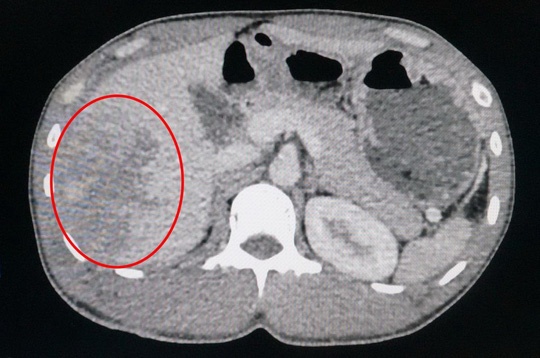

Một người đàn ông đang bơm bánh xe tải thì bất ngờ bánh xe nổ gây vỡ gan, suýt mất mạng.